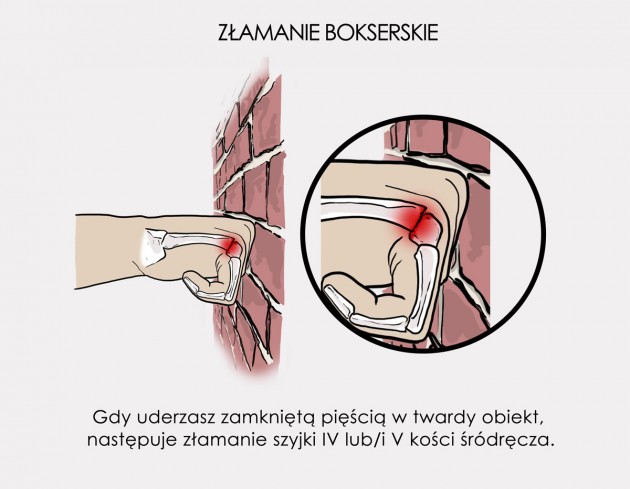

Złamanie bokserskie

Złamanie bokserskie to schorzenie dość częste, występujące nie tylko w sporcie, ale i w życiu codziennym. Złamanie bokserskie to schorzenie dotyczące IV i V kości śródręcza, a dochodzi do niego gdy pacjent uderzy zaciśniętą pięścią w twardy obiekt.

Lekarze podzieli złamanie bokserskie na 2 podtypy:

Złamanie bokserskie to schorzenie dość częste, występujące nie tylko w sporcie, ale i w życiu codziennym. Złamanie bokserskie to schorzenie dotyczące IV i V kości śródręcza, a dochodzi do niego gdy pacjent uderzy zaciśniętą pięścią w twardy obiekt.

Lekarze podzieli złamanie bokserskie na 2 podtypy:

- Złamanie Brawler’a – następuje, gdy do złamania dochodzi tylko w obrębie szyjki V kości śródręcza.

- Złamanie typu Bar Room – to złamanie w obrębie szyjki IV lub/i V kości śródręcza.

Typowe objawy towarzyszące złamaniu to ból, krwiak i obrzęk w obrębie IV i V kostki.